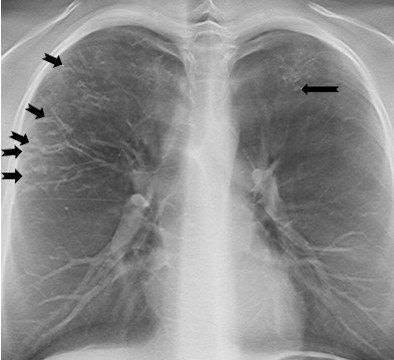

On a tomosynthesis section, cylindrical bronchiectases in the right upper lobe and small mucus plugs in a tree-in-bud pattern in the periphery of the lobe (arrows) are seen, but are not apparent on the AP radiograph. In the apical part of the left upper lobe, small cylindrical bronchiectases and mucus plugs (arrow) are seen.

On a tomosynthesis section, cylindrical bronchiectases in the right upper lobe and small mucus plugs in a tree-in-bud pattern in the periphery of the lobe (arrows) are seen, but are not apparent on the AP radiograph. In the apical part of the left upper lobe, small cylindrical bronchiectases and mucus plugs (arrow) are seen.While typical pulmonary changes in cystic fibrosis such as mucus plugging, bronchial wall thickening, and bronchiectases are superior in tomosynthesis images compared with a chest radiography, they are not superior to images produced by a CT scan. Depth resolution is inferior, and objects such as intravenous lines, tubes, or other devices generate artifacts within the area that is the most distant from the tomosynthesis sections. As a result, the lung parenchyma may be obscured. Localized air trapping and mosaic pattern cannot be adequately evaluated with tomosynthesis.